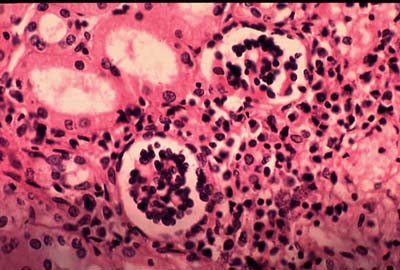

Có một sự thật mà không phải ai cũng biết, đó là Napoléon từng phải đối mặt với tình trạng nhiễm trùng do sán trong máu. Những ký sinh trùng khét tiếng này gây ra một tình trạng gọi là bệnh sán máng (hay còn gọi là bệnh bilharzia) và để làm cho mọi thứ tồi tệ hơn, không chỉ một mà có hơn nửa tá loài thuộc chi Schistosoma coi con người là vật chủ của chúng.

Sự lây nhiễm xảy ra qua nước bị nhiễm ấu trùng Schistosoma (được gọi là cercariae). Ấu trùng xâm nhập vào da của vật chủ, sau đó qua máu, đến gan, ruột, đường tiết niệu và nhiều bộ phận khác của cơ thể. Các triệu chứng thường gặp của bệnh sán máng là ngứa da, đau bụng, tiêu chảy … Tuy nhiên, ở giai đoạn sau, nó có thể gây ra các vấn đề sức khỏe nghiêm trọng như phì đại gan, tiểu ra máu, nhiễm trùng tuyến tiền liệt, xơ hóa bàng quang và vô sinh.

Theo WHO, hơn 230 triệu trường hợp mắc bệnh sán máng đã được báo cáo, kể từ khi căn bệnh này được phát hiện lần đầu tiên vào năm 1851. May mắn là ở thời điểm hiện tại, nhiễm trùng có thể được điều trị dễ dàng bằng cách sử dụng một loại thuốc chống ký sinh trùng.